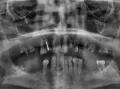

К сожалению, другого варианта нет. Или имплантация, или съёмный кламмерный протез.

Для любых других несъёмных конструкций не позволяют условия (недостаток зубов).